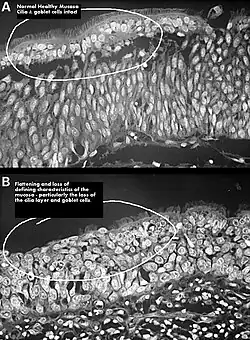

Squamous metaplasia of nasal respiratory epithelium.

The cause of ENS may be due to the body not accepting the new airflow in the nasal passages following surgical procedures, indicated sometimes by an improvement in sensation after placement of wet cotton in place of the missing turbinate. The nose is an incredibly complex area of the body and one that has been very poorly researched in terms of the effects on aerodynamics from surgical procedures. In many patients with ENS, the airflow is modeled as being more turbulent with less laminar flow across the mucosa. This reduced amount of mucus in the nose can also be attributed to the change in airflow often resulting in dry cool air hitting the back of the patient's throat.[23]

One possible cause may be changes to the nasal mucous membrane and to the nerve endings in the mucosa resulting from chronic changes to the temperature and humidity of the air flowing inside the nose, caused in turn by removal or reduction of the turbinates.[3][7] The TRPM8 receptor, responsible for the sensation of nasal openness (patency), is activated by high-speed airflow, which cools the nasal lining through evaporation. This cooling triggers signals to the brain, making breathing feel easier. Nasal passage enlargement alters airflow, reducing turbulence and mucosal cooling which results in reduced sensation of airflow. Studies confirm that without the inferior turbinate, air conditioning in the nose is less effective.[7]